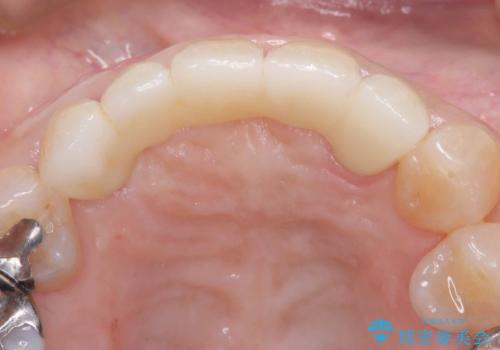

- 税込2,057,000円(インプラント(3本)手術とオールセラミッククラン5本分の費用全て込み)費用は治療当時の料金となります

今回のケースでも、しっかりと固定が得られたため、手術は1回で終了し、短期間でオールセラミッククラウンまで装着することができました。患者様も術後の痛みはなく、処方した痛み止めも服用されなかったとのことです。

これだけ大きな病変があったにもかかわらず、痛みがなく短期間で治療が終わったことに加え、被せ物の色も周囲の歯に調和し美しく仕上がったことに、大変ご満足いただけました。